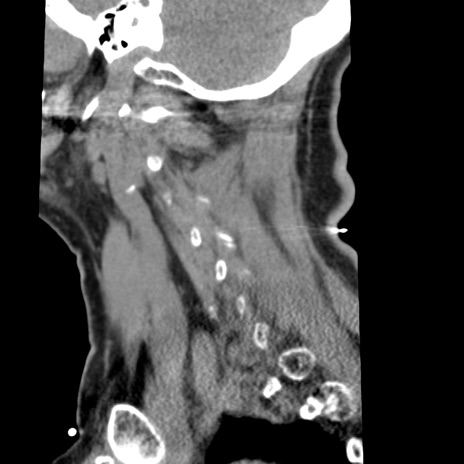

症例50 頚椎CT(矢状断像)

異常所見と診断は?

冠状断像